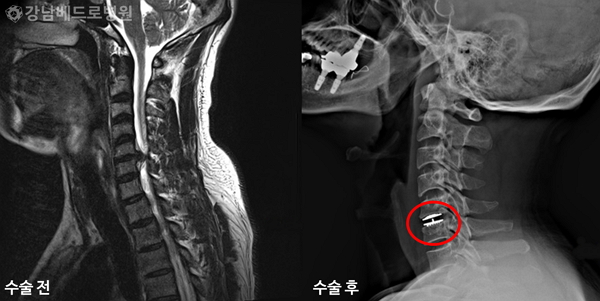

★ 목디스크 치료방법 ★